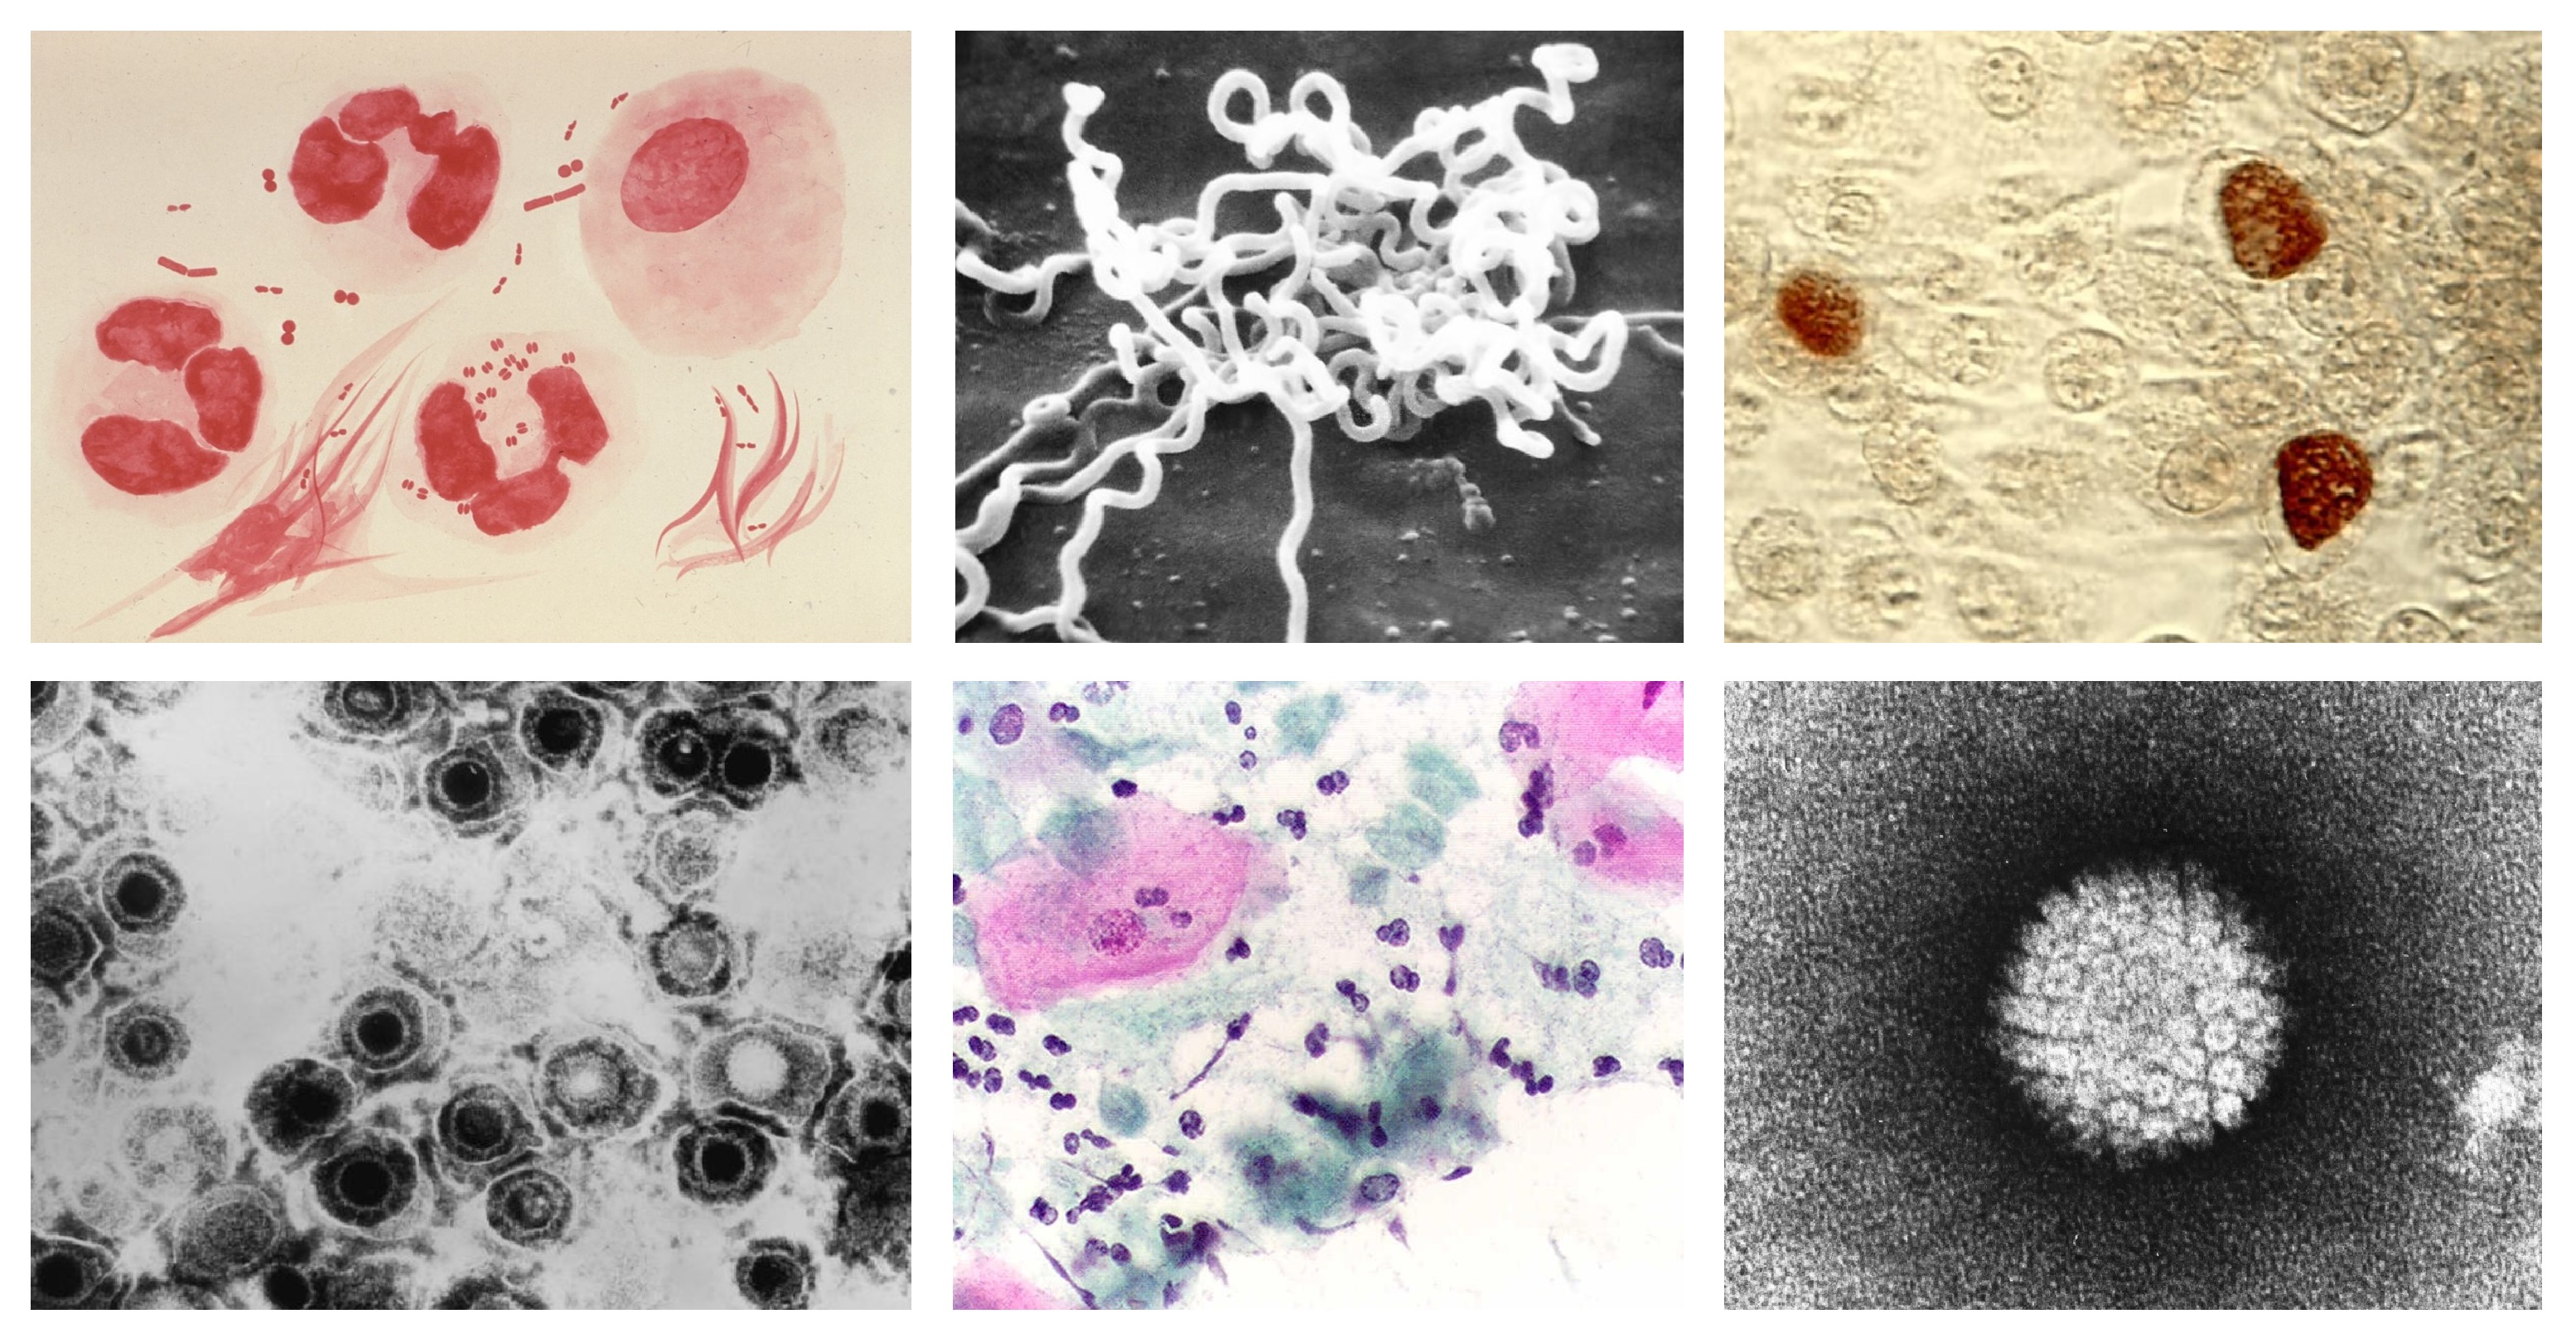

Un organoide de riñón es una estructura tridimensional, de unas micras de tamaño, cultivada en el laboratorio a partir de células madre humanas. Aunque no es un órgano completo, reproduce muchas de sus estructuras y funciones principales. Gracias a estas características, los organoides permiten estudiar cómo se desarrolla el riñón, probar nuevos fármacos y, en el futuro, se espera que puedan ser utilizados para reparar tejidos renales dañados o mejorar órganos destinados al trasplante. El estudio describe, por primera vez, un método sistemático y escalable de ingeniería genética para producir miles de estos organoides renales humanos.

Los resultados son fruto del trabajo de más de una década dedicada a estudios de medicina regenerativa y bioingeniería de órganos. El equipo de investigación ha conseguido combinar por primera vez organoides renales humanos con riñones porcinos vivos, conectados a máquinas de perfusión normotérmica. El uso de estos dispositivos, utilizados habitualmente en el quirófano para mantener el órgano vivo y oxigenado fuera del cuerpo antes de un transplante, ha permitido insertar organoides humanos dentro de los riñones porcinos y evaluar en tiempo real su integración y función.

El equipo de investigación observó que, después de 24 y 48 horas del trasplante, los organoides humanos persistían integrados en el tejido renal porcino, mantenían su viabilidad y no desencadenaban ninguna respuesta inmune significativa. El riñón trasplantado continuaba funcionando con normalidad, y no se detectaron signos de daño ni toxicidad.